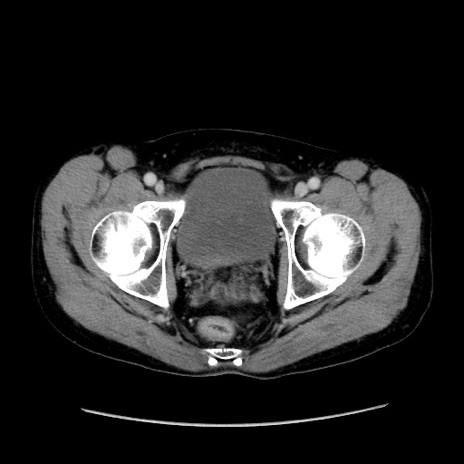

症例37(横断像)

【症例】40歳代 男性

【主訴】腹痛

【現病歴】4時間ほど前に電車に乗車中に臍部上より腹痛出現。徐々に増悪し起立困難となり、救急外来受診。生ものは数日食べていない。今朝お雑煮を食べた。

【身体所見】BT 36.8℃、BP 117/84mmHg、HR 91/min、SpO2 97%、苦悶様、腹部:臍上部広範囲圧痛あり、反跳痛±

【データ】WBC 8100、CRP 0.03